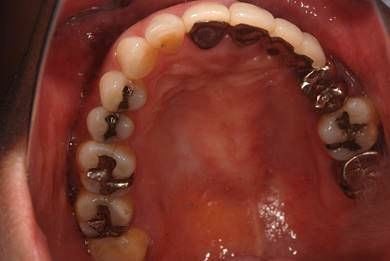

| 性別/年齢 | 女性 / 45歳 | ||||||||||||||||||||||||||||||||

| 主訴 | 以前治療した歯の歯ぐきから出膿。他の歯科でインプラントかブリッジしか方法がないが、骨の状態からインプラント治療は無理かもしれないと言われたことに不安を感じ、セカンドオピニオンを求めて来院。 | ||||||||||||||||||||||||||||||||

| 治療方針 | 保存不能の歯を抜歯し、インプラント治療にて機能的・審美的回復を行う。 | ||||||||||||||||||||||||||||||||

| 治療内容 | インプラント1本、ハイブリッドセラミッククラウン1本 | ||||||||||||||||||||||||||||||||

| 総治療費 | 310,905円 | ||||||||||||||||||||||||||||||||

| 治療期間 | 5ヶ月 |